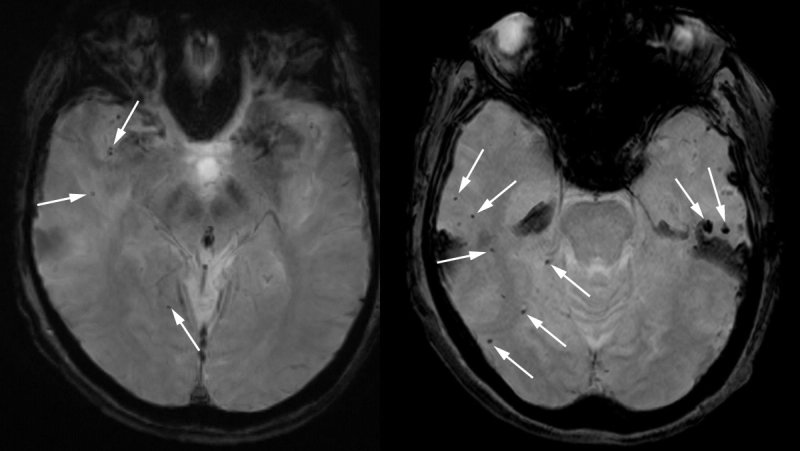

Le scansioni cerebrali hanno mostrato dozzine di aree di sanguinamento e gonfiore del cervello, così estese che le pieghe caratteristiche della corteccia cerebrale erano "fuse e schiacciate" in parti sostanziali del suo cervello, afferma Charidimou, che chiama questo "un caso da manuale di ARIA grave, sia la presentazione clinica che le manifestazioni nelle scansioni". Data l'assenza di altre potenziali cause del danno cerebrale indicato nella cartella clinica, aggiunge, il lecanemab quasi certamente è il colpevole.

"La paziente aveva un vasto gonfiore del cervello con alcune piccole aree di sanguinamento che le hanno fatto avere un attacco e alla fine l'hanno fatta morire", afferma Schrag, che è uno specialista CAA. "Sono convinto che questo sia stato un effetto collaterale del lecanemab".